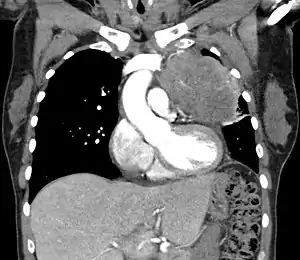

| Thymic carcinoma seen on CT. | |

Diagnosis of thymic carcinoma is based on a combination of clinical, radiologic, and biopsy findings. Most early cases are asymptomatic and found incidentally on chest radiographs as a mass in the anterior mediastinum. Further evaluation consists of additional imaging, such as CT, MRI, and PET, and tumor biopsy, which is the gold standard and provides the definitive diagnosis.[5] Biopsy may be done prior to surgery by fine needle aspiration or during the surgery with concomitant evaluation by the pathologist.[8] Other carcinomas with malignant spread to the thymus are on the differential diagnosis and must be excluded, as they may appear similar to thymic carcinoma on histopathological examination. [3]